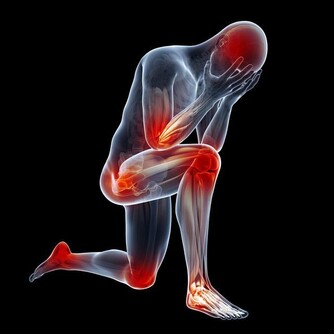

要想保持健康, 必須清除以下幾種體內毒素。

1、體內廢氣典型表現:

經常腹脹,而且放屁很臭。

長期積累的結果:腹痛,潰瘍惡化,